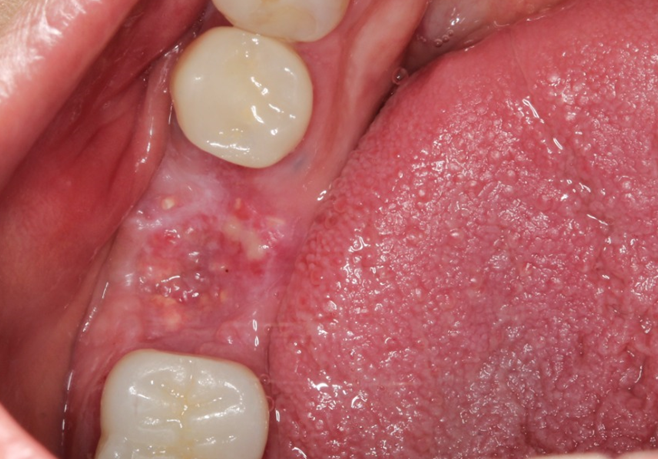

Através deste relato de caso observou-se que por meio da avaliação dos exames clínicos e radiográficos de maneira criteriosa pode-se chegar ao diagnóstico definitivo de casos de fratura/trinca radicular, permitindo um planejamento adequado do caso. A realização de exodontia atraumática seguida de implante imediato, possibilitando a preservação da anatomia alveolar e preservando a estrutura óssea, apresenta-se favorável para o paciente, pois reduz o número de intervenções cirúrgicas. Além disso, o uso da técnica de regeneração óssea guiada na Implantodontia, promovendo o preenchimento deGAP nos alvéolos com biomaterial de origem bovina, favorece o aumento ósseo. Por fim, a utilização de uma membrana não absorvível (Cytoplast) intencionalmente exposta ao meio bucal é uma alternativa previsível de tratamento nos casos de preservação alveolar.